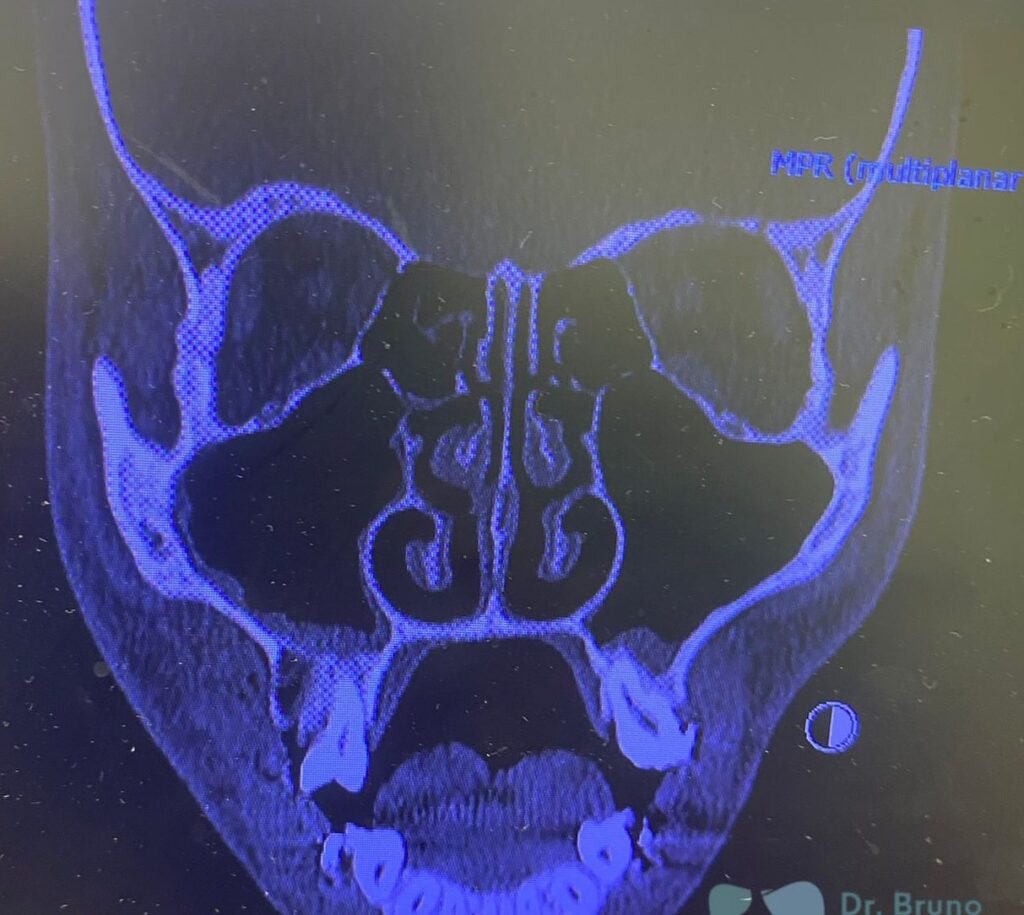

A Patologia Oral e Maxilofacial é a especialidade responsável pelo diagnóstico e tratamento de doenças que afetam a boca, mandíbula e estruturas faciais. Atua na identificação de lesões, cistos e tumores, garantindo diagnóstico preciso e tratamento adequado para preservar a saúde bucal e geral do paciente.